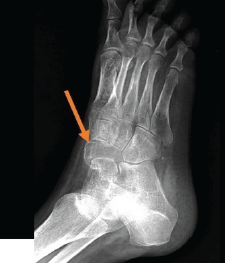

Surgical Management of Painful Os Vesalianum: A Case Report and Literature Review

Venkataramana Kuruba , Vignesh Chandrasekar , Abhinay Vadlamudi , Elandevan Gunasekaran , V T Abraham , A R Nataraj